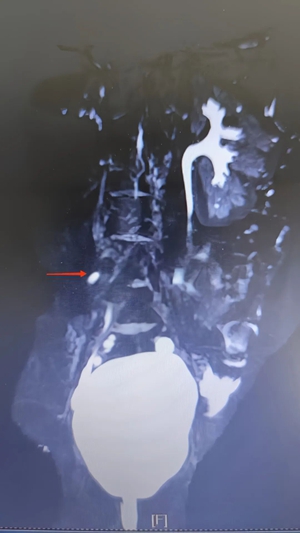

接診后,小兒泌尿外科主任高強(qiáng)憑借豐富的臨床經(jīng)驗(yàn),并未將小玉的癥狀簡(jiǎn)單歸為排尿控制能力差。結(jié)合患兒長(zhǎng)期漏尿的病史,醫(yī)生為小玉完善了超聲、MRI 尿路成像(MRU)、CT 等一系列檢查,最終明確診斷為右腎發(fā)育不良伴輸尿管異位開(kāi)口。

單側(cè)腎發(fā)育不良示意圖

輸尿管異位開(kāi)口示意圖